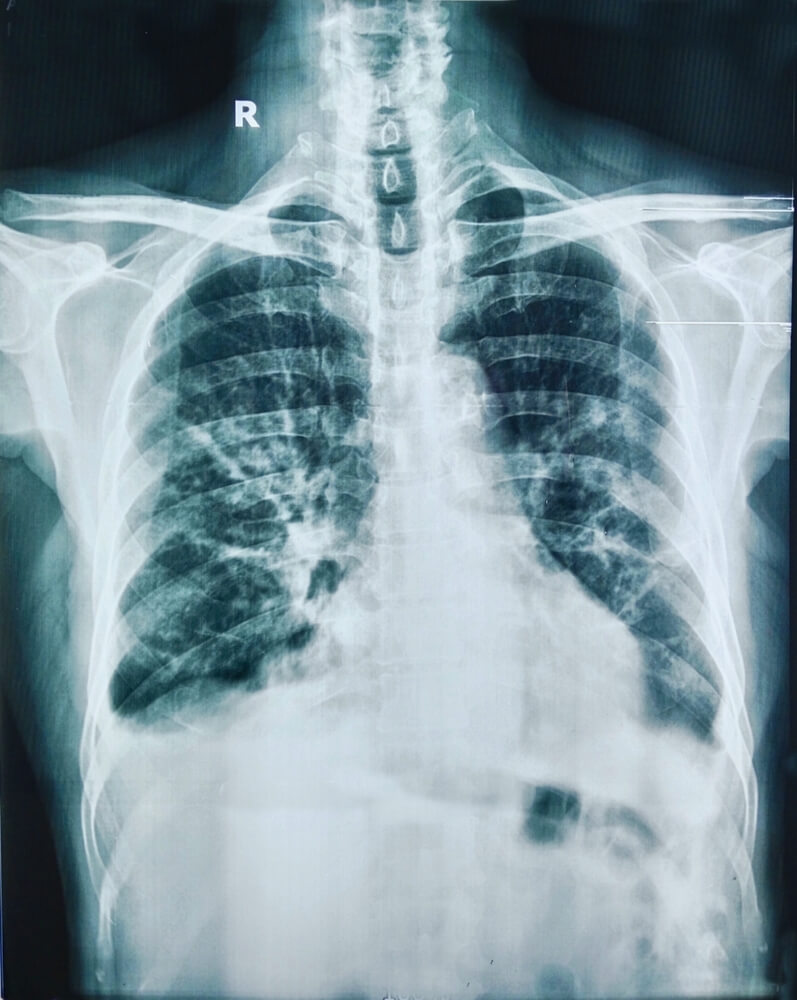

Увидев изменения в лабораторных данных, получив положительные туберкулиновые тесты, терапевт назначает инструментальные исследования. Большей информативностью отличается лучевая диагностика: рентген легких и КТ органов грудной клетки.

Рентгенолог обнаруживает очаги поражения, детально их описывает. На основании чего терапевт уже понимает, что за болезнь, насколько она поражает легкие. Направляет пациента к фтизиатру.